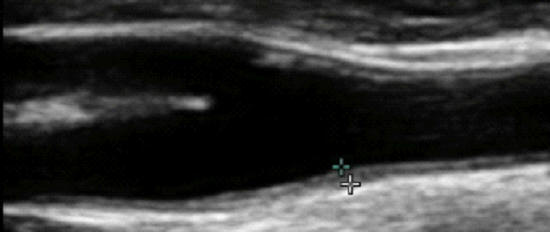

Carotid Artery Intima-Media Thickness (brackets, above), the combined thickness of the endothelial and muscular layers of the Common Carotid Artery, reflects your current propensity to form plaque and risk of future atherosclerotic events (heat attack, stroke, etc.). IMT increases with age, on average at 0.01 mm/year, and IMT rate of change relates to risk factor control efficacy. Slow progression or stabilization of IMT reflects good risk factor control. Conversely, rapid IMT progression indicates that we have more work to do. All phenomena shown to increased CV risk will increase IMT while effective therapeutic efforts will attenuate IMT (discussed in detail elsewhere on this website).

While IMT is systemic, atherosclerotic plaque is focal, and above we see mild plaque at the level of the carotid bulb. Change in arterial physiology (risk factor control) determines IMT, which in turn determines rate of plaque progression and overall atherosclerotic risk.